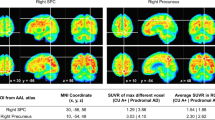

Automatic spatial normalization and Aβ-index

Images were spatially normalized to MNI space using a PET driven image registration utilizing the adaptive principal component template method described by Lilja et al.23. The complete details of the principal component approach can be found in the original publication. Briefly, the adaptive template is created based on tracer specific principal component images calculated by singular value decomposition. A synthetic template, ISynthetic, can then be modelled as a linear combination of the first principal component image, IPC1, and the second principal component image, IPC2, i.e.

where a positive Aβ-index yields a template with a more Aβ-positive appearance and a negative Aβ-index yields a template with a more Aβ-negative appearance. The spatial normalization optimizes both spatial parameters and the Aβ-index when registering images to the adaptive template defined in MNI space. In the present study pre-existing synthetic templates derived from clinical trial phase 2 studies were used for spatial normalization of 18F-Florbetapir45,46 and 18F-Flutemetamol47. The values for Aß-index were averaged across the two tracers. The registration method is similar to that reported by Lundqvist et al.48. The difference lies in the creation of the adaptive template. In the implementation of CortexID, these authors use a linear regression model whereas the method described by Lilja et al.23 utilizes eigenvalue decomposition. Visual comparison of resulting templates suggests greater accuracy with the latter method.